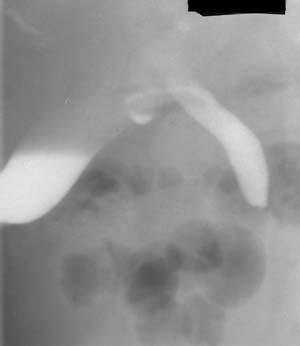

Рис. 3. При заполнении желчных протоков определяется обтурация желчного протока конкрементом (Слева). При контрастировании желудка и 12-перстной кишки определено расстояние между уровнем обтурации и сфинктером Одди (Справа).